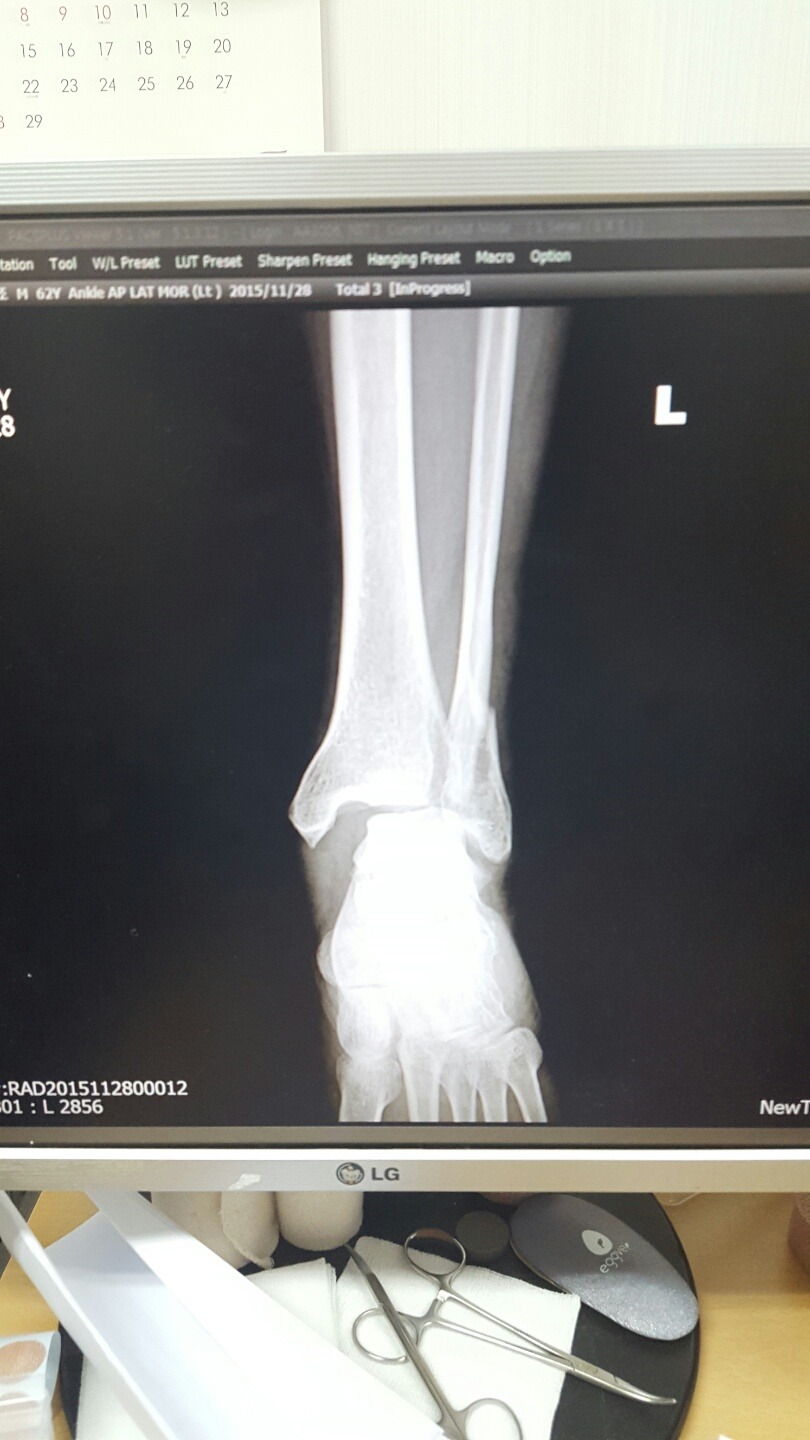

8시30분경 골절사진 촬영 정형외과과장이 경비골골절 탈구(발목이 빠짐)확인. MRI촬영 인대파열확인